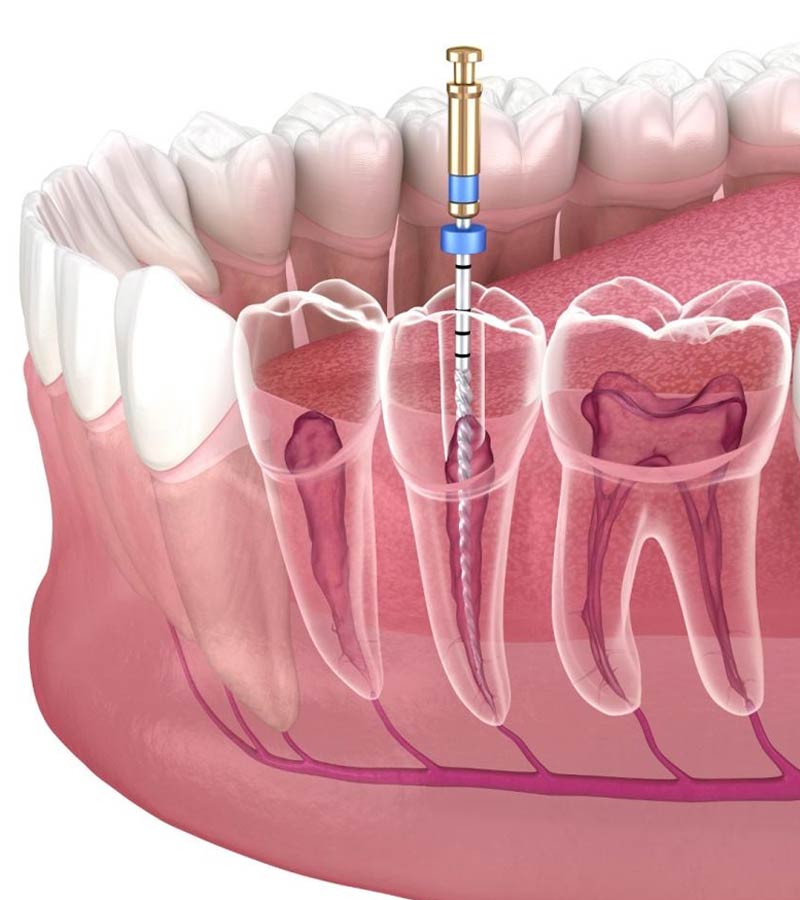

1. Evaluare clinică și radiologică

Radiografia este obligatorie pentru:

- identificarea anatomiei canalelor

- determinarea lungimii de lucru

- evaluarea infecției periapicale

- verificarea rezultatului final

În anumite cazuri se recomandă și CBCT 3D pentru vizualizare detaliată.

5. Instrumentarea canalelor

Cu ace manuale sau rotative din NiTi (nichel-titan), care oferă:

- flexibilitate mare

- precizie

- adaptare la canale curbe